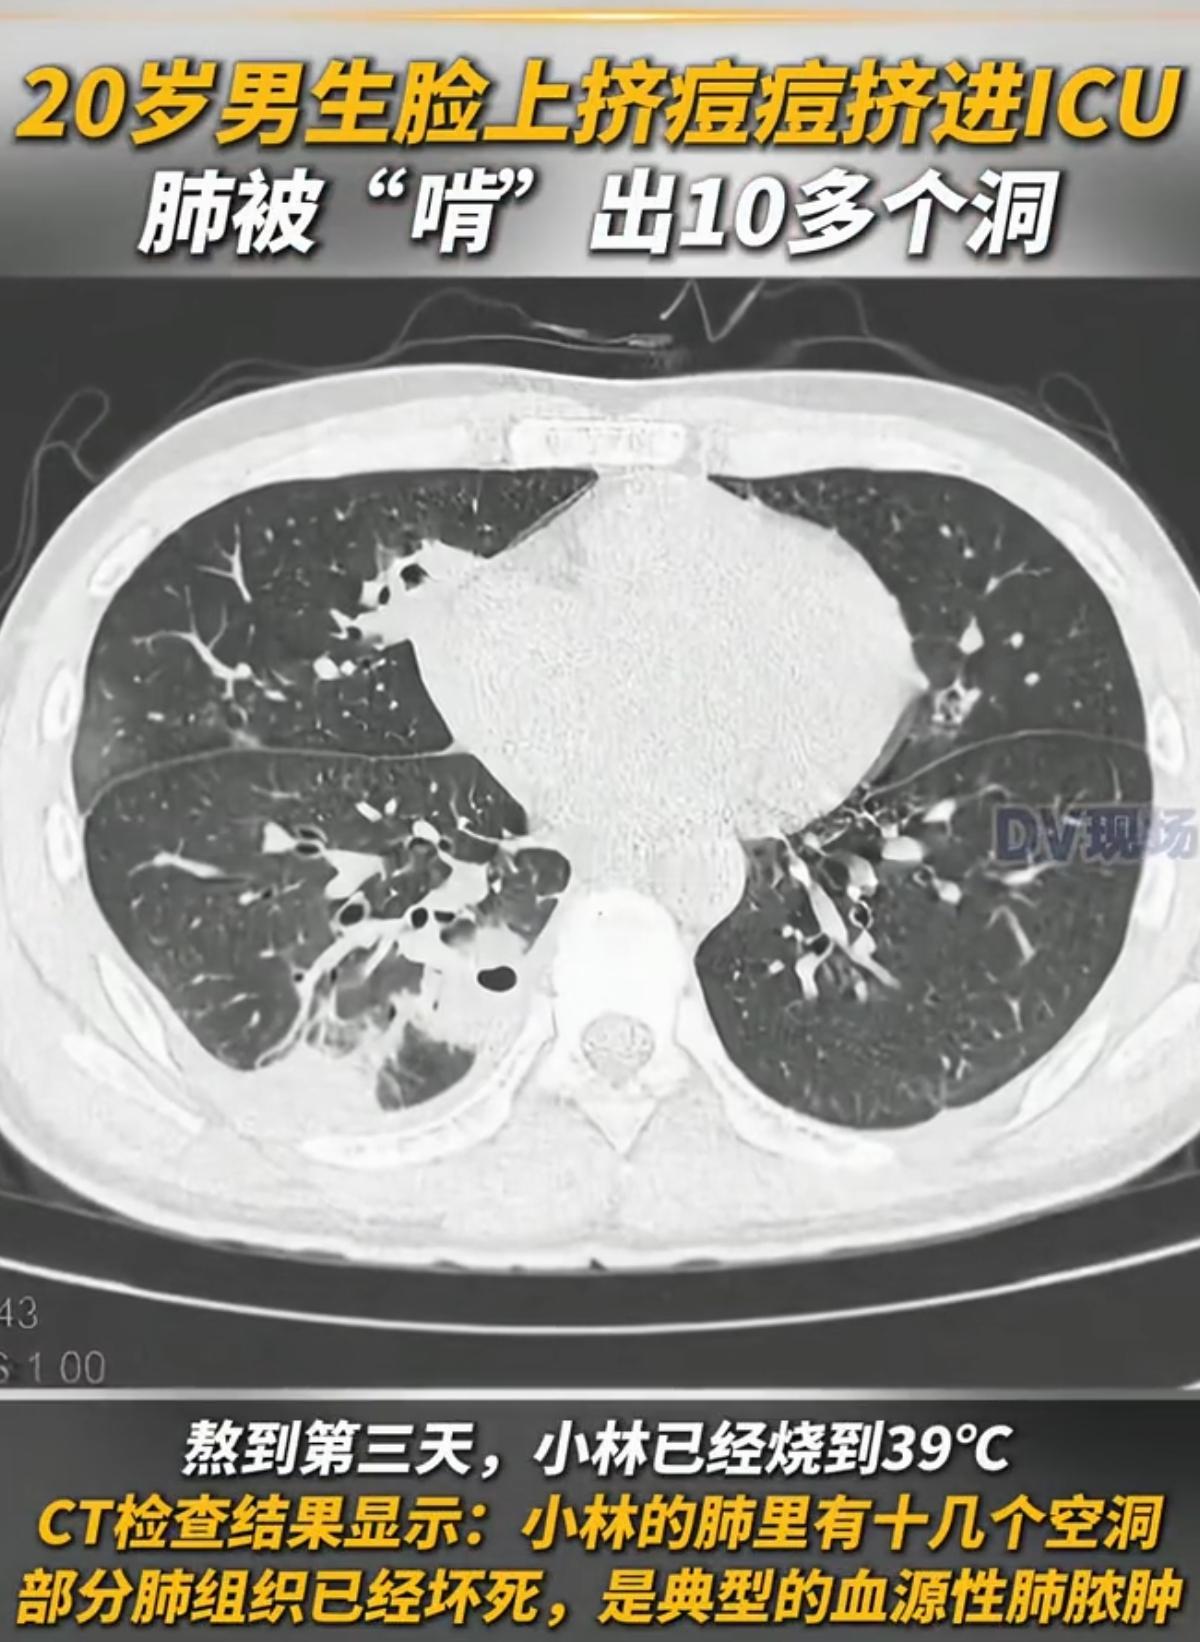

原来老一辈人说的, 都是有道理的! 某个20岁的大学生,因为在脸上挤痘痘,结果把自己挤进icu。 想想就恐怖,就仅仅挤了颗小小的痘痘,竟然引发了败血症!明明这是件很常见的事情而已。 以前我爸妈还一直跟我强调,不要乱把脸上痘痘挤掉,我也没听他们的,有痘就挤出来,现在想想,真是我命大啊! 我有这想法,也不能怪我吧,毕竟谁能想到,细菌会从痘痘进到体内啊,还危险度极高。 查了下,从科学上讲,三角区的痘痘最危险,千万别碰它,等这些痘痘自己消除就好,没必要去挤掉,因为这个三角区的血管是直通的,没办法堵住细菌。 所以说,有时候老一辈人的话,还是得听啊。